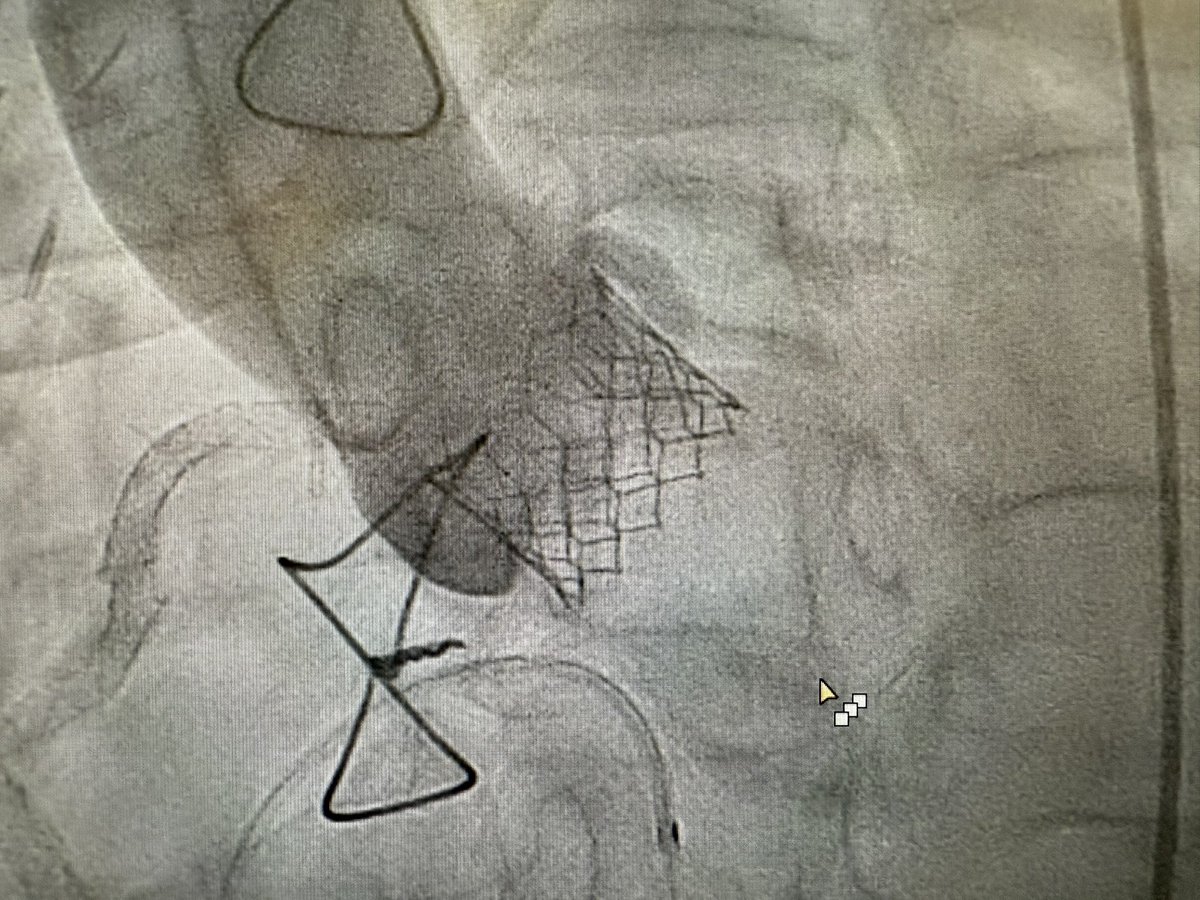

Featuring the use of #S3Ultra 20mm in small annulus. Plus 1cc on the initial balloon inflation followed by double tap post. No leak with peak to peak of 0. New era of #tavi #tavr with perfect result even in complex anatomy #structuralheart @EdwardsLifesci

Our #NUHCS structural heart team showcased a live TAVI case at the West China Minimally Invasive Cardiovascular Conference 2025, led by Asst Prof Ivandito Kuntjoro & Asst Prof Jimmy Hon, to highlight advances in balloon-expandable valves for small annulus cases.

#NUHCS took part in the 19ᵗʰ Oriental Congress of Cardiology 2025, where our NUHCS specialists Asst Prof Ivandito Kuntjoro, Asst Prof Jimmy Hon Kim Fatt, & Adj A/Prof William Kong Kok Fai, performed a complex bicuspid TAVI case which was broadcasted live to the conference.